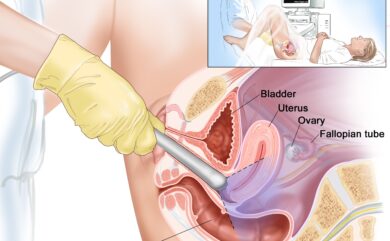

Transvaginal Ultrasound in Dehradun

Transvaginal Ultrasound (TVS) for Non-Gynaecological Conditions – Himalayan Diagnostics, Dehradun…